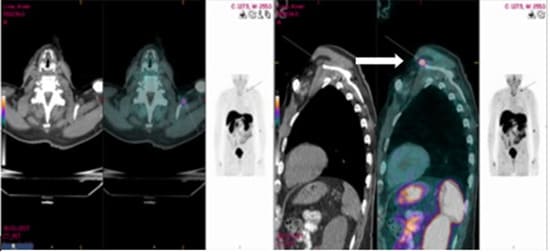

An 81-year-old man who was referred to the endocrinological clinic after he was diagnosed with osteopenia (T score of minus -1.5 in the spine and minus -1.2 in the femur). Five years previously, he was treated by a family physician with alendronate, vitamin D and calcium. He was referred to orthopedic consultation due to intense left hip pain. Upon his arrival he underwent physical examination and pelvic computed tomography (CT), which did not show any pathological findings. Medical history did not disclose any chronic diseases or hereditary bone disease apart from the history of bullet shrapnel fragments in different parts of his body which were the result of past military injuries. Laboratory results disclosed normal calcium levels 9.9 mg/dl (normal range 8.810.20 mg/dl) low phosphorus 2.10 mg/dl (normal range 2.5-5 mg/dl) and mild elevated alkaline phosphatase 144 U/L (normal range 30-120 U/L), 25 hydroxy vitamin D test results were normal, 121 nmol/l (normal range 39-160 pmol/l). The clinical findings which revealed low phosphorus levels and elevated alkaline phosphatase levels, raised our suspicion regarding TIO. FGF23 levels in the blood were elevated to 150.8 pg/ml (normal range 23.2- 95.4 pg/ml). Repeated 24-hour urine phosphate collection disclosed relatively high phosphate excretion 959 mg/24h (normal range 400-1300 mg/dl) (Figure 6). Imaging with 68Gallium DOTANOC PET/CT revealed pathologic uptake in the upper aspect of the left shoulder adjacent to the coracoid process. No mediastinal or axillary lymphadenopathy was observed (Figure 5). The patient was referred to the orthopedic surgical department, due to suspected phosphaturic mesenchymal tumor. Since an MRI could not be performed, because of the remaining bullet fragments in the body, the tumor and its anatomical position were evaluated by an ultrasound examination. After the evaluation, the patient underwent wide resection of the tumor. Histopathological examination of the tumor disclosed fat tissue with proliferation of bland spindle cells with numerous blood vessels, amorphous matrix deposition and several calcifications without atypia and mitosis, with free surgical margins. These findings were consistent with a benign phosphaturic mesenchymal tumor (Figure 7). Three months post-surgery, phosphorus levels and a 24-hour phosphorus collection were normalized.

Figure 5: 68Gallium DOTANOC PET/CT demonstrating a small soft tissue nodule with pathologic uptake situated adjacent to the superoanterior aspect of the coracoid process (arrow).